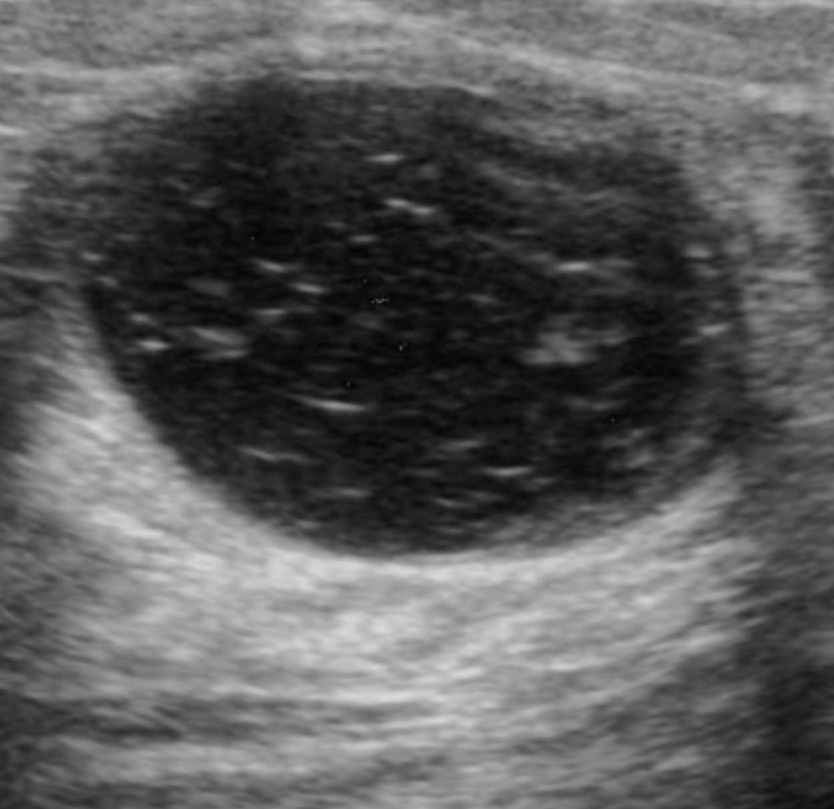

Ultrasound imaging of a palpable breast lesion. Marked hypoechogenicity with immobile echogenic foci (representing calcifications)

• Hypoechoic echotexture